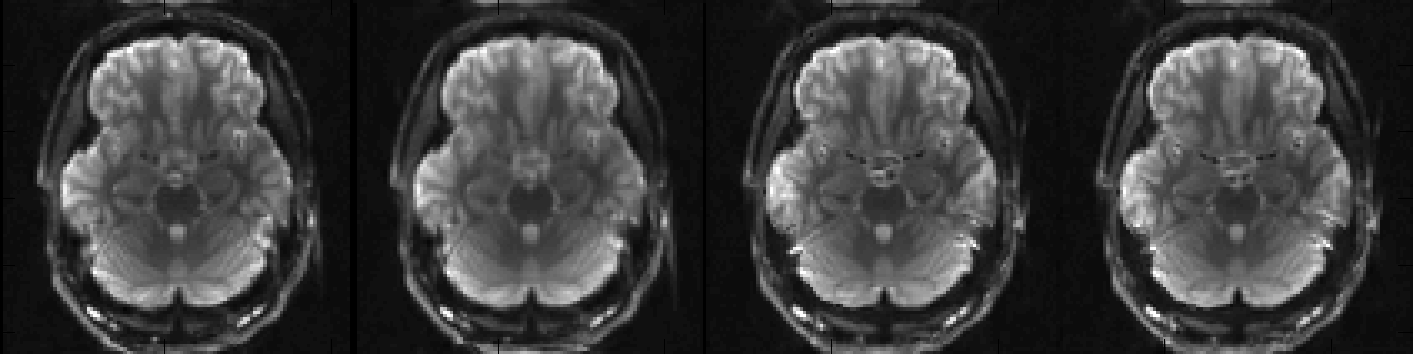

EPI images acquired with different PE-directions after correction

I think we can agree that that looks quite good and that we have no reason to think that topup ran into any problems. Let us now look at my_topup_results_movpar.txt to see if we were right in our suspicion that there had been some movement.